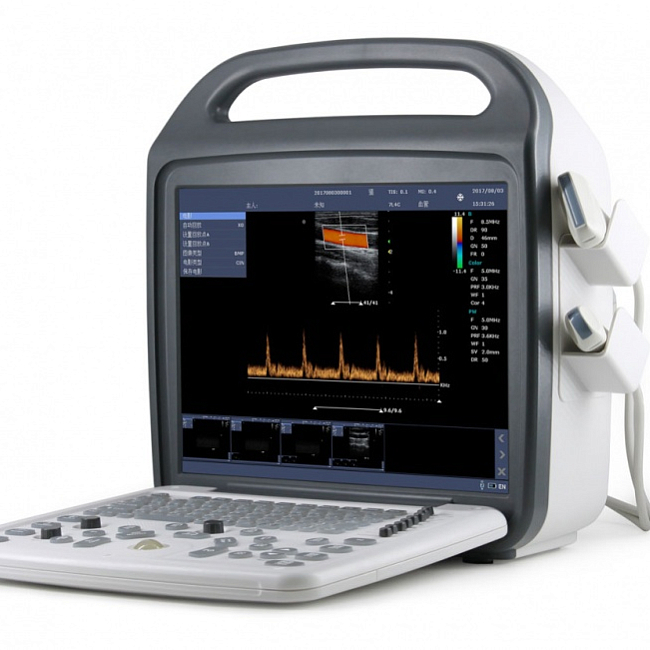

Аппарат ультразвуковой SonoScape S9 Pro

цена: 3 213 000 руб.Портативная, переносная, диагностическая УЗИ система. Области применения: абдоминальные исследования, акушерство и гинекология, кардиология, неврология, травматология и ортопедия, урология, эндокринология, ангиология, педиатрия, неонатология, транскраниальные исследования, онкология. Класс аппарата: высокий. Конструктивное исполнение: переносной. Производитель SonoScape. Китай.подробно заказать